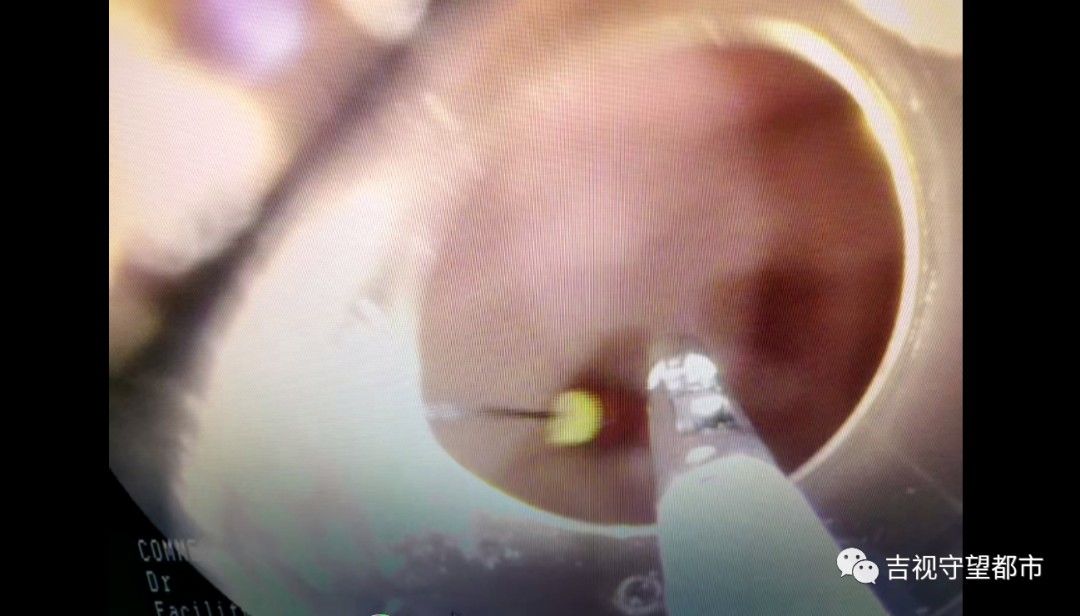

这个取出过程中,我们就需要保护这种消化道黏膜,因为那个针特别尖锐,取出的过程中,如果要是再刺伤这个消化道黏膜,可能会造成二次损伤,所以我们当时就在内镜前端装了一个透明帽,然后用这个透明帽把这个针放到这个透明帽里,这样就把黏膜保护起来,所以取完之后,孩子的消化道黏膜没有任何损伤。